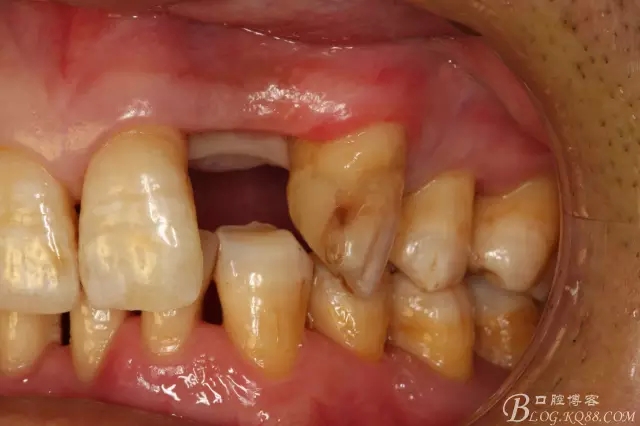

圖3.術(shù)前口內(nèi)照片:正面觀閉口位

圖4.左側(cè)側(cè)面觀,22間隙正常,23近中輕度扭轉(zhuǎn)